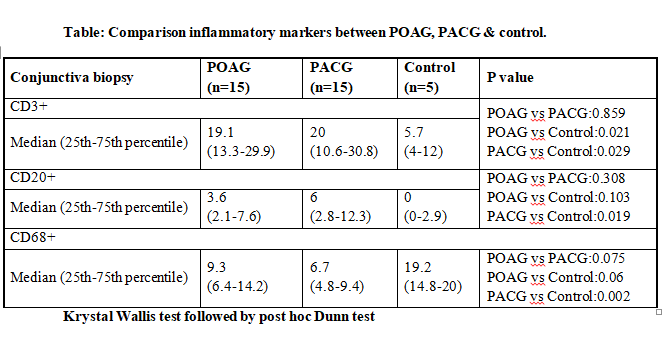

Cellular profile in PACG with median CD68+ at 6.7 was significantly less than controls 19.2(p=0.002) & non significantly less than POAG with median 9.3

Cellular profile in PACG with median CD20+ at 6 was significantly more than controls at 0 (p=0.019) & non significantly more than POAG with median at 3.6

Cellular profile in PACG with median CD3+ at 20 was significantly more than controls at 5.7 (p=0.029) & POAG with median at 19.1 was significantly more than control 5.7(0.021). POAG vs PACG was not significant.

Cellular profile in PACG with median goblet cells at 3 was non significantly less than POAG at 10 & equal to control at 3.

Fibrous pattern was seen in 26% of glaucoma cases (27% patients of POAG, 20% patients in PACG). Inter group comparison NS. Cells positive to CD3+ (T Lymphocytes) were at 5.7 (control), 19.1(POAG) & 20 (PACG). Comparison of POAG

with control (p=0.021) and PACG with control (p=0.029) was statistically significant. Comparison of POAG & PACG was NS. Cells positive to CD20+ (B Lymphocytes) were at 0 (control), 3.6 (POAG) & 6 (PACG). Comparison of PACG with

controls was statistically significant (p=0.019), while POAG vs controls was not statistically significant. POAG vs PACG did not achieve statistical significance. Cells positive to CD68+ (Macrophages) were 19.2 (control), 9.3

(POAG) & 6.7 (PACG).

Comparison of POAG group with control was NS, however that of PACG with control did show statistically significant difference (p=0.002). POAG vs PACG was not statistically significant. Number of goblet cells were 3 (control), 10

(POAG) & 3 (PACG). Comparison of both POAG & PACG with controls was NS. POAG vs PACG was NS.